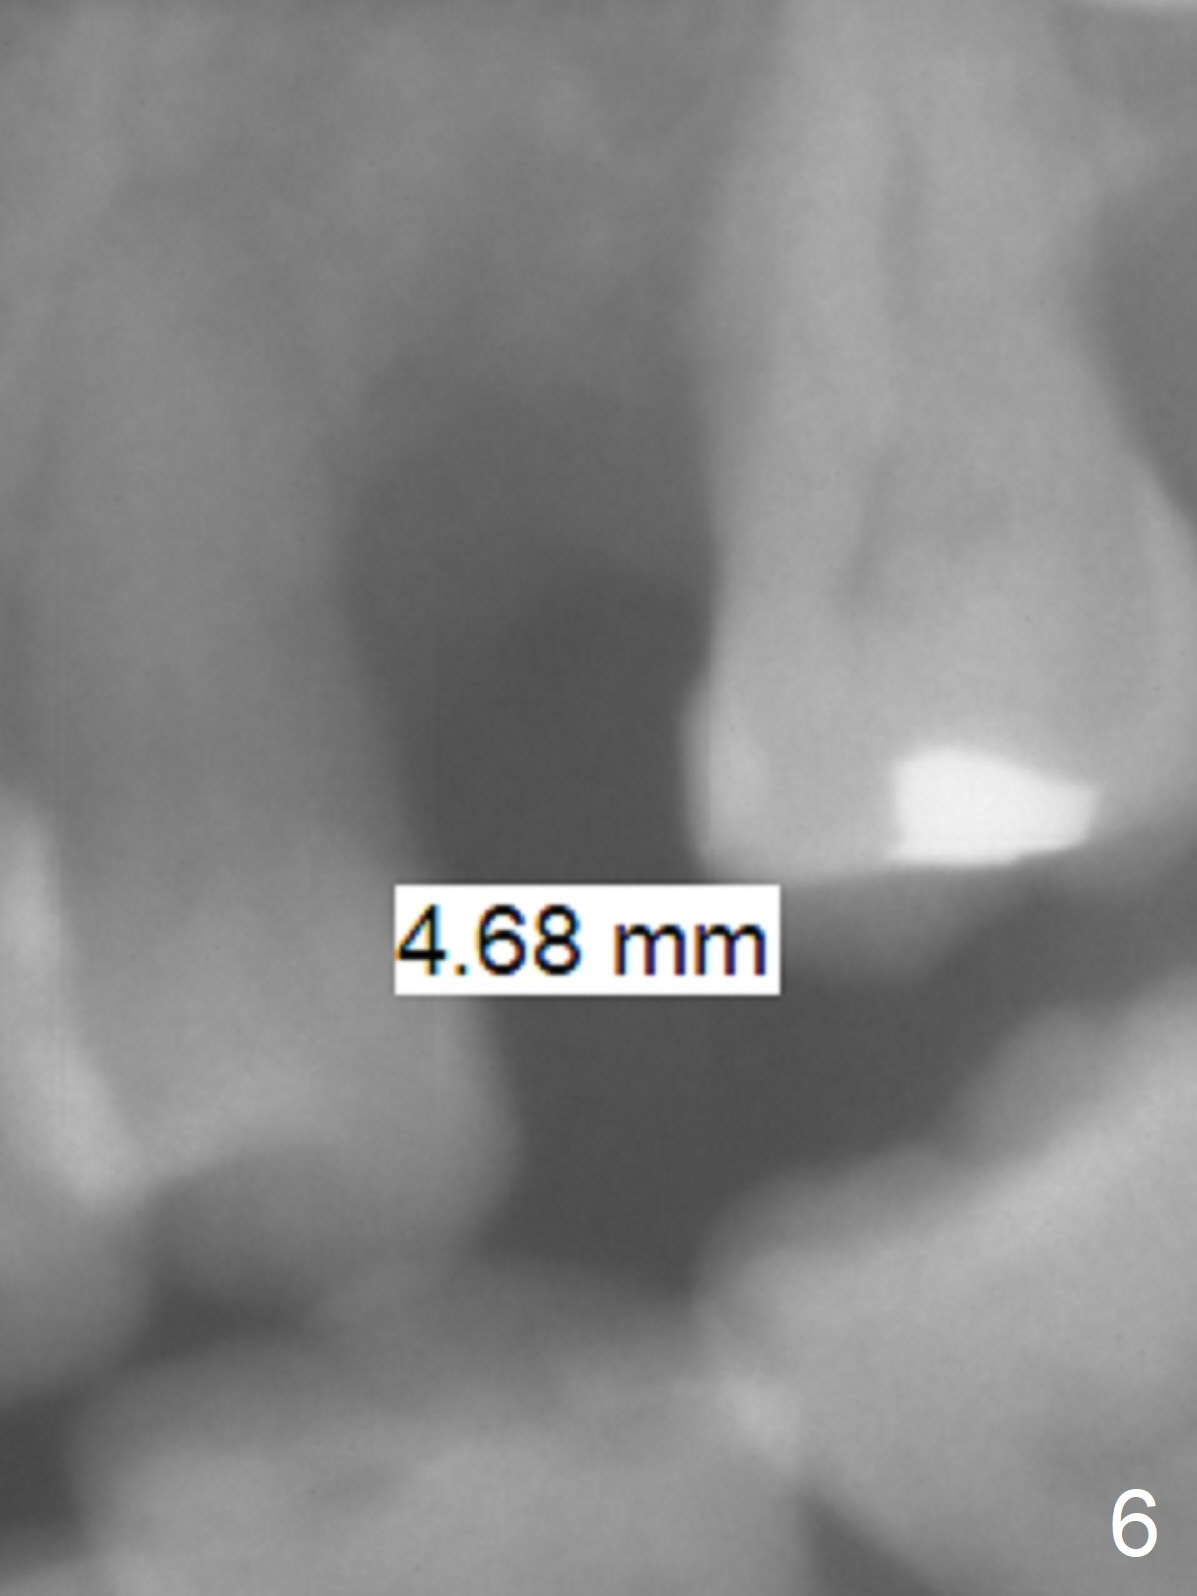

A 54-year-old woman had #14 extracted in China 1 year ago (Fig.1,5). The tooth #15 has undergone mesial shift and tilt (Fig.2,4, as compared to Fig.3). The edentulous space is too narrow for implant placement (Fig.6). It appears that traditional orthodontic appliance should be placed from UR6 to UL7 in addition to a mini-implant distal to UL7. Take Alginate impression before treatment. Since the implant at UR7 is placed apparently too deep, a band will be placed when it is initially osteointegrated (6-8 weeks postop). Fabricate a well-fit provisional with permanent cementation before banding. In fact, brackets and bands are placed between UR3 and UL7. In 6 months, the meisodistal space at #14 is enough to place an implant (Fig.7).